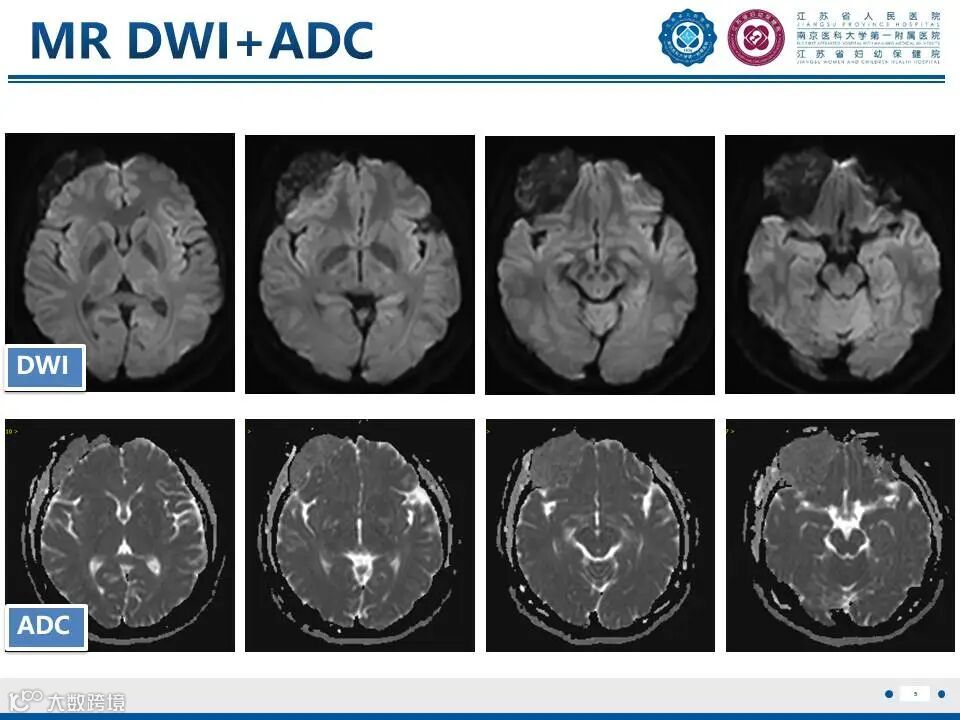

颅骨骨纤维异常增殖症——颅骨上的编织骨

颅骨骨纤维异常增殖症——颅骨上的编织骨 鼎湖影像